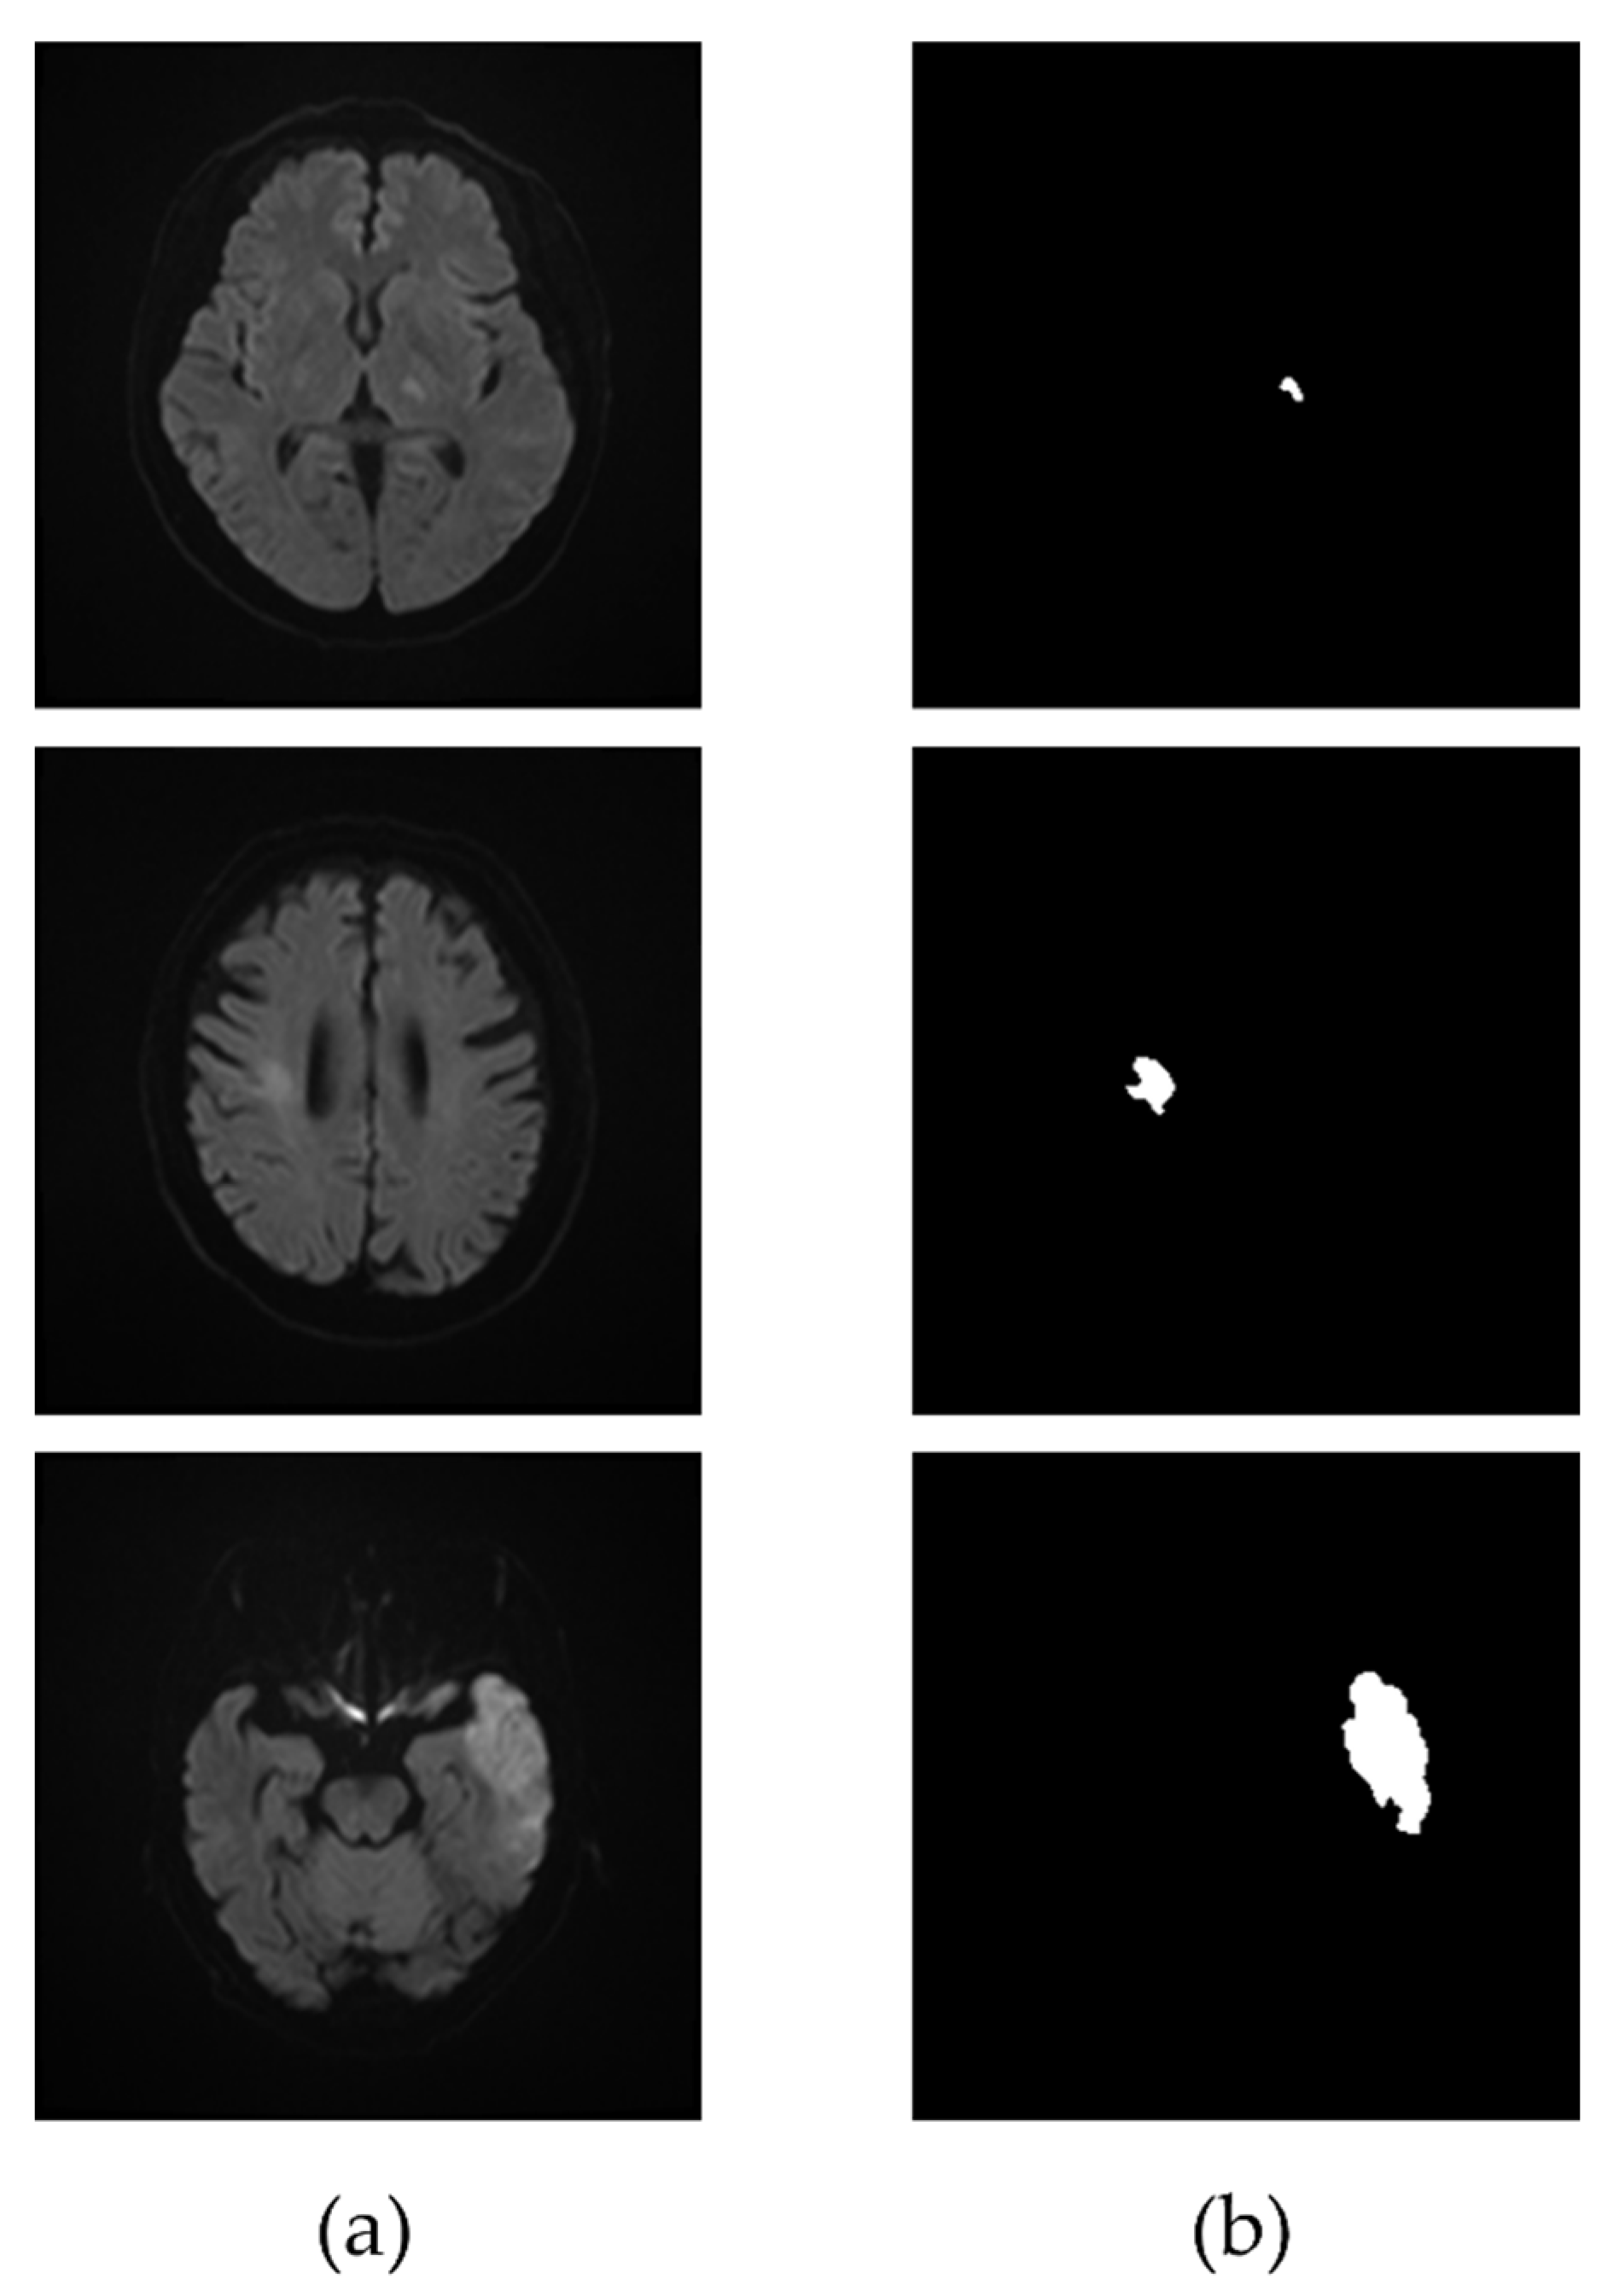

2.4. Extraction of Infarcted Region

3.2. Extraction of the Infarcted Regions